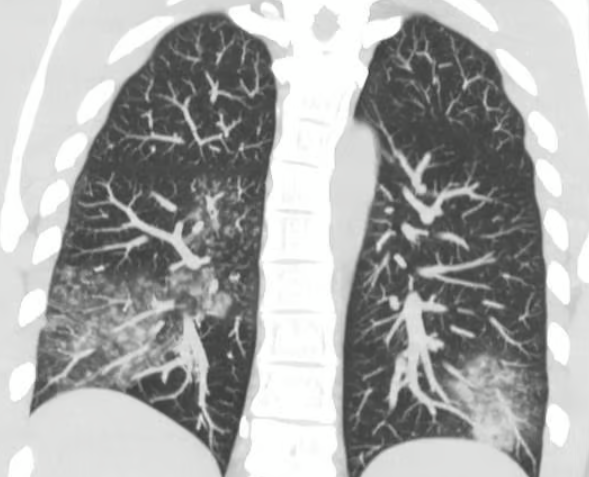

Lungs affected by metapneumovirus. Photo: Olha Holubovska